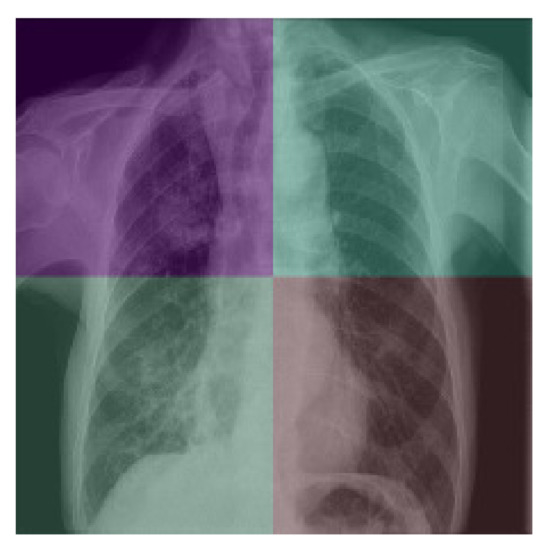

Ultimately, we decided to use another method very similar to Grad-CAM called Score-CAM because of its smoother, more consistent, and less noisy heatmaps [23]. Score-CAM finds the weights connected to individual pixels and filters of the image, thus finding which parts of the images have the most influence on the output of the CNN. Using Score-CAM, we generated heat maps of our X-rays that showcased the areas in the lung that xRGM-NET recognized as important for determining whether the patient was infected with COVID-19 or not. Areas in red represent opacities or spots in the lung that might indicate COVID-19 while areas in blue are parts that represent normality. As seen in Figure 7, the two COVID-19 positive patients have large opacities on the left sides of their lungs and these are shown in the Score-CAM images with dark red ovals. However, on the healthy patients, there is a distinct lack of these red markers and the lungs are shown to be healthy.

Figure 7.

Score-CAM on various X-rays. X-rays from [7,8].